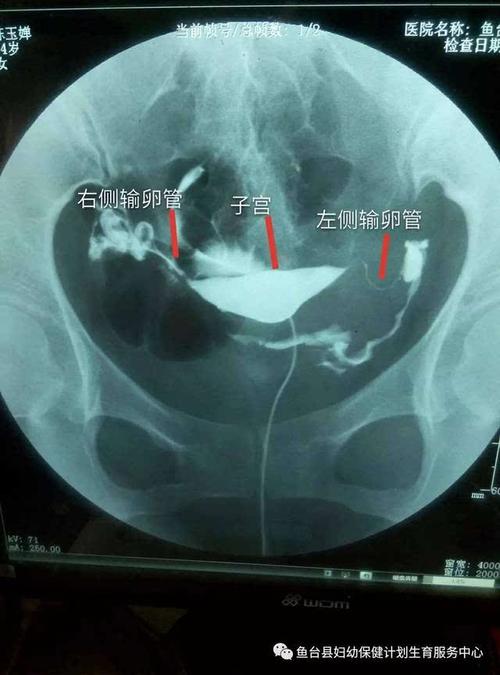

输卵管肿大怎么治疗最好

输卵管肿大怎么治疗最好,如果患上输卵管肿大,想要恢复生育的话,是需要经过医学的测试才可以得出结论的,那么输卵管肿大怎么治疗最好呢?